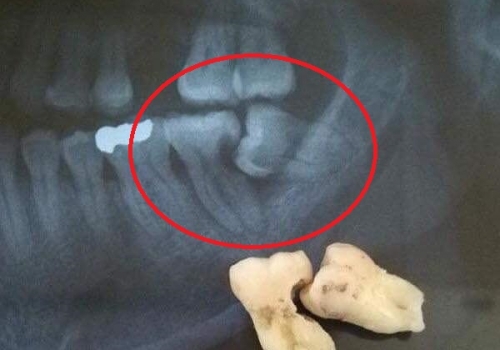

Normal halda insanın diş sırasında hər çənədə iki ədəd olmaqla, ümumilikdə dörd agıl dişi mövcuddur. Ağıl dişinin çıxması bəzi şəxslərdə heç bir kliniki əlamət və ya şikayətə səbəb olmasa da, bir çox hallarda müəyyən kliniki əlamətlərlə öyünü biruzə verir. Bu əlamətlər əsasən çənənin arxa tərəfində təzyiq, çənəni açıb baglama əsnasında agrı və məhdudlaşma kimi özünü göstərə bilir. Bu hallarda mütəxəssis konsultasiyasının önəmi olduqca böyükdür. Belə ki müayinə zamanı cərrah-stomatoloq kliniki və radioloji dəyərləndirmə apararaq dişin dogru pozisiyada yerləşib yerləşmədiyi, dişləmə çıxma ehtimalını, agıl dişinin çənəyə görə ölçüsü və çənə darlıgı kimi durumları dəyərləndirərək tətbiq edilməli olan müalicə taktikasını müəyyən edir.